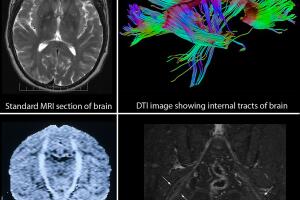

La presión arterial es la fuerza de la sangre contra las paredes de los vasos sanguíneos y se mide en milímetros de mercurio (mm Hg), explica la American Heart Association.

Se expresa en dos cifras, la primera llamada presión sistólica es aquella que hay cuando late el corazón, y la segunda o más pequeña, llamada presión diastólica, cuando el corazón descansa entre latidos.